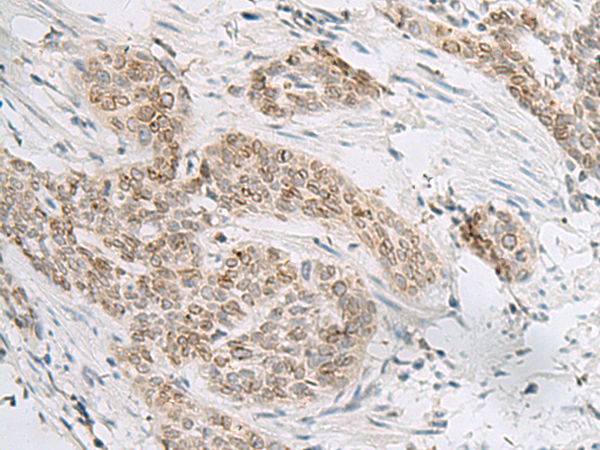

分类: 科研抗体货号: P13586别名: ABBP1; HNRPAB应用: WB,IHC反应种属: Human, Mouse